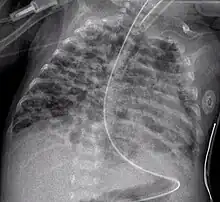

• The air bronchogram sign, where branching radiolucent columns of air corresponding to bronchi is seen, usually indicates air-space (alveolar) disease, as from blood, pus, mucus, cells, protein surrounding the air bronchograms. This is seen in Respiratory distress syndrome[9]